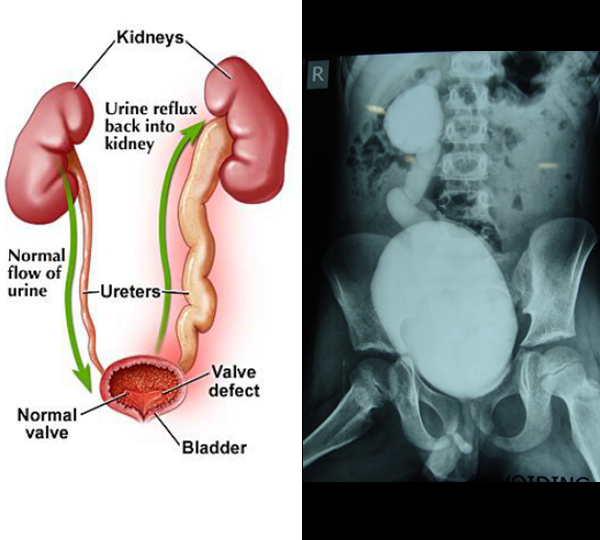

Vesico-ureteric reflux (VUR) occurs when the valve between the ureters (the tubes that carry urine away from the kidneys) and